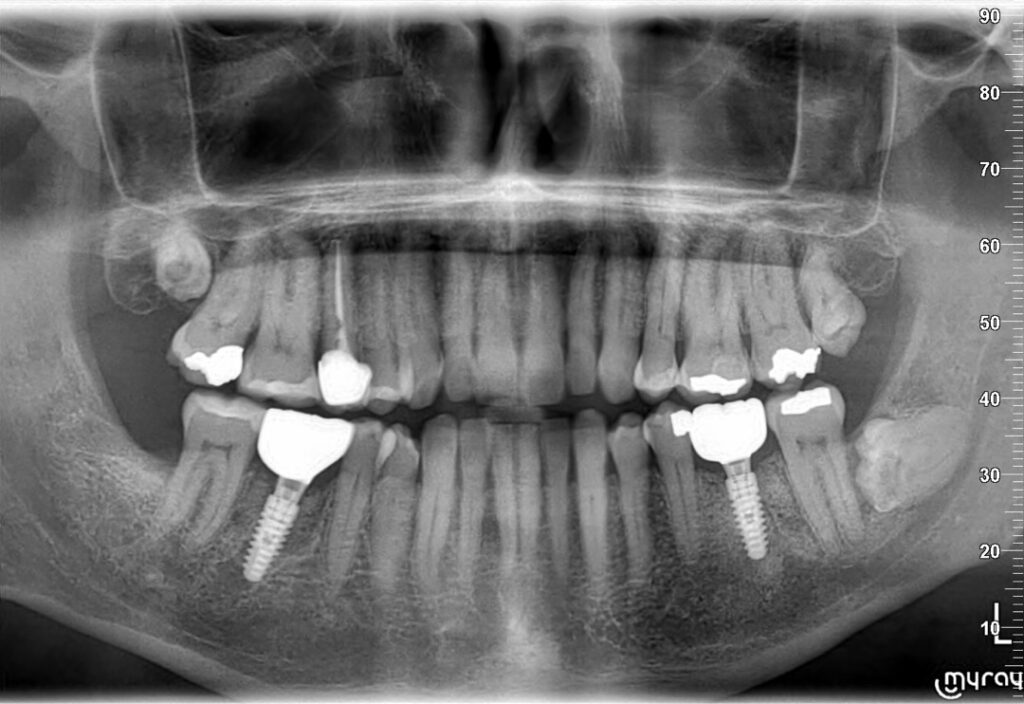

- Controlar radiográficamente el hueso alrededor del implante.

- Pérdida de hueso alrededor del implante.

- Ausencia total de un plan de mantenimiento.

- Problemas en el diseño de la prótesis que dificultaban la higiene.

Pudimos reconducir el caso, pero con más trabajo del que habría hecho falta si desde el principio se hubiera controlado mejor el hueso cervical y el mantenimiento.